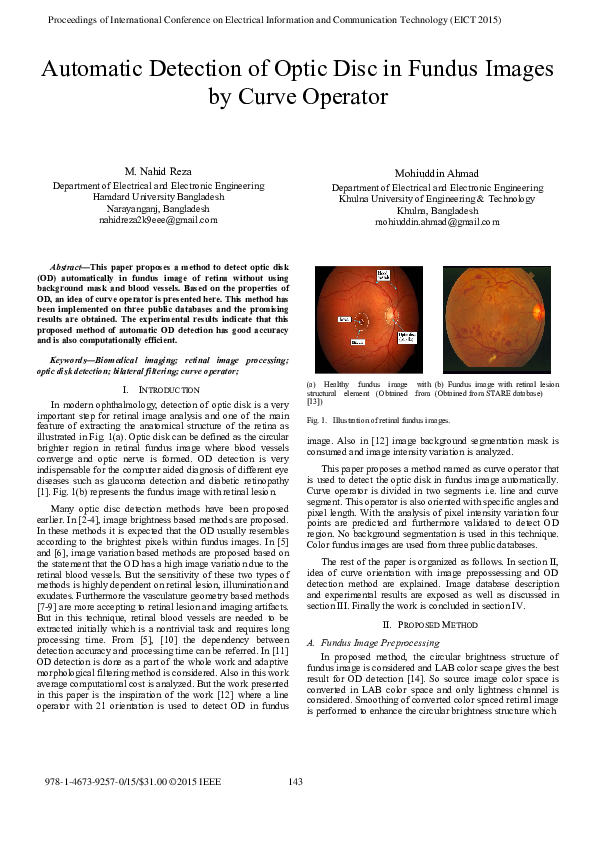

(PDF) Automatic detection of optic disc in fundus images by curve Optic Disk Explanation An optical drive is a device that reads and/or writes data onto a disc. To read/write data onto a disc, an odd uses a laser diode to receive and send electromagnetic waves. The surface of the disk is encoded with data in the. What is an optical disk? What is an optical disk? An optical disk is a flat, circular. Optic Disk Explanation.